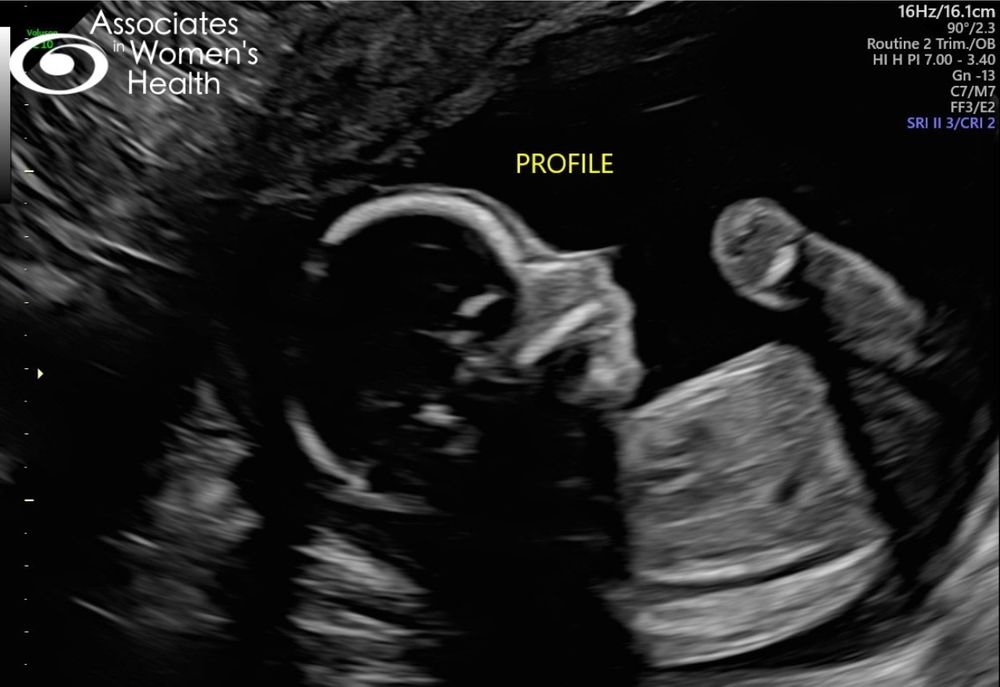

19+1, узи

Увидела своего пирожка в деталях сегодня, походу он будет ещё активнее брата 🙈 вроде все ттт в норме. Самочувствие значительно лучше первого триместра, но периодически мучает тошнота по вечерам.